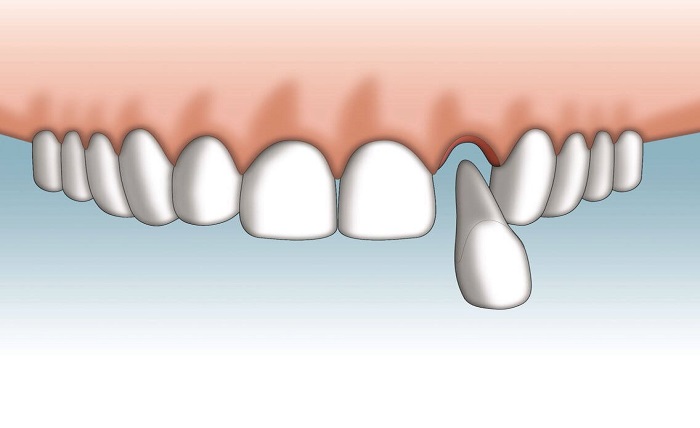

First, locate the tooth. When you pick it up, be very careful to only touch the crown, which is the shiny, white part you normally see when you smile. Avoid touching the root at all costs. The root is covered with delicate periodontal ligament cells that are essential for reattachment. Touching or scrubbing the root can damage these cells and make reimplantation impossible.

The best place for a knocked-out tooth is back in its socket. If possible, gently try to place the tooth back into its original position.

- Carefully align it with the empty socket.

- Push it in gently. If it doesn’t go in easily, don’t force it.